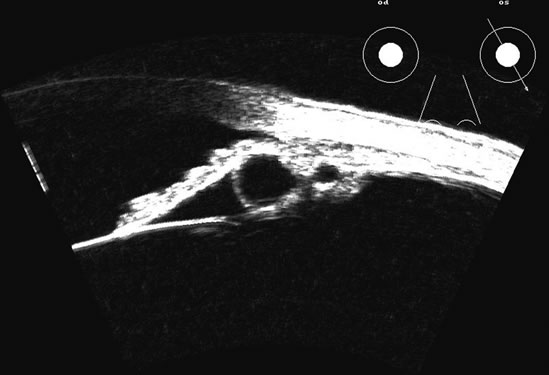

Hypotony is easily diagnosed by direct measurement of intraocular pressure, but the underlying cause is difficult to evaluate.11 High-frequency ultrasound scans can easily reveal separation of the ciliary body and the sclera. This allows different forms of hypotony to be determined—for example: tractional with membrane attached; primary as idiopathic, often inflammatory or hemorrhagic; and dehiscence secondary to iridodialysis or scleral perforation (Fig. 6).

Fig. 6. Hypotony of the eye generally is easily diagnosed by a separation of the ciliary body from the sclera. We have noted several types of such separation, such as tractional, primary (idiopathic), and dehiscence secondary to iridodialysis or scleral perforation, as in filtration procedures. In our series, greater than two clock hours of separation is typical of hypotony. The lower figure shows a concomitant thickening of the retina-choroid complex, also seen in hypotony (arrows). Long-standing hypotony typically has a shortened globe and possible retinal or choroidal separation.